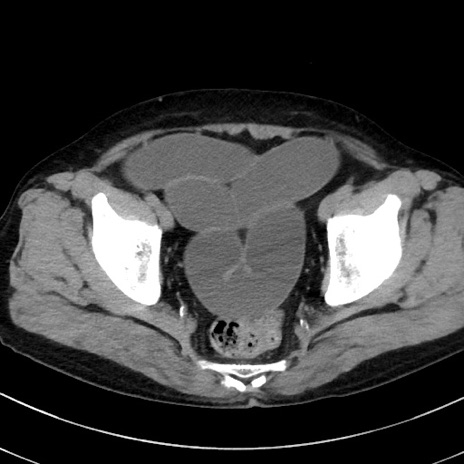

症例38(横断像)

【症例】70歳代 男性

【主訴】腹痛・嘔吐

【現病歴】昨晩より、嘔吐・腹痛あり。今朝になっても嘔吐あり。来院。

【既往歴】心臓バイパス手術、開腹胆摘、腸閉塞

【身体所見】BP 107/71mmHg、HR 116/min、腹部:平坦、軟、下腹部に軽度圧痛あり。反跳痛なし。

【データ】WBC 15100、CRP 0.32